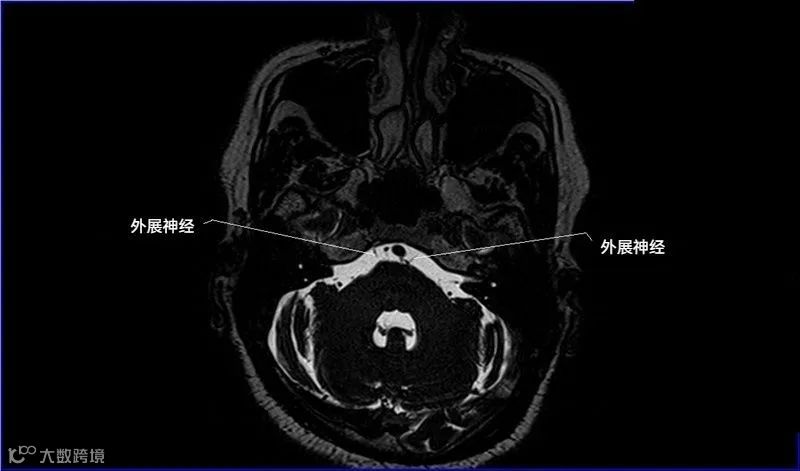

十二对脑神经口诀

一嗅二视三动眼,四滑五叉六外展,

七面八听九舌咽,迷走及副舌下全。